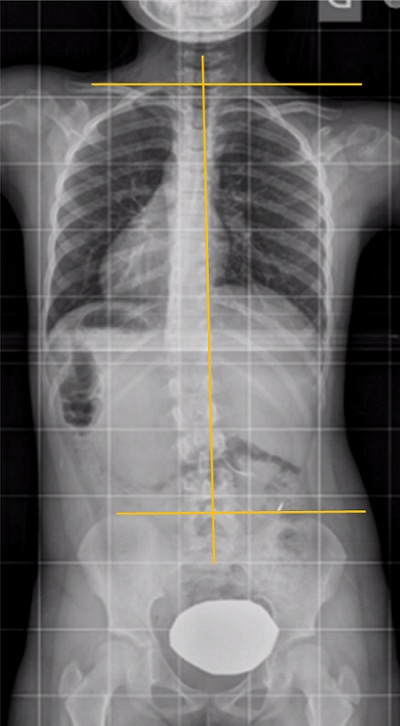

Conseguida una proyección correcta, vista de frente, la columna vertebral sana, será recta. Los pedículos vertebrales se verán en posición simétrica respecto al cuerpo vertebral donde asientan, con las apófisis espinosas en el centro entre ambos.

La línea plomada (línea imaginaria vertical que va de la apófisis espinosa de la última vértebra cervical a la correspondiente de la última vértebra lumbar) pasa por todas las espinosas. Sin embargo, Cobb, tal como apunta en su libro Staheli, reconoce variantes de hasta 10° como situaciones en las que no se ha comprobado que produzcan inestabilidad de ningún tipo en el niño ni en el adulto1.

El borde superior de la pelvis, las crestas iliacas y el de las cabezas femorales pueden no estar en línea si el paciente tiene una discrepancia de longitud. Pero las clavículas y los hombros, en el paciente bien posicionado y sano, deben estar a la misma altura.

Las costillas se visualizan simétricas con inclinación curva y espacio intercostal simétrico en los dos hemitórax.

Pero, a veces ocurre que la columna no se ve perfectamente derecha4. ¿Cómo reconocer que se trata de una escoliosis posicional o actitud escoliótica? (Figura 4): los hombros deben estar a la misma altura, porque la articulación del hombro y la pseudoarticulación, escápulo-torácica, se mueven sin influir en la posición de la columna. Ascienden o descienden la clavícula con su movimiento, pero el raquis puede mantenerse perfectamente recto.